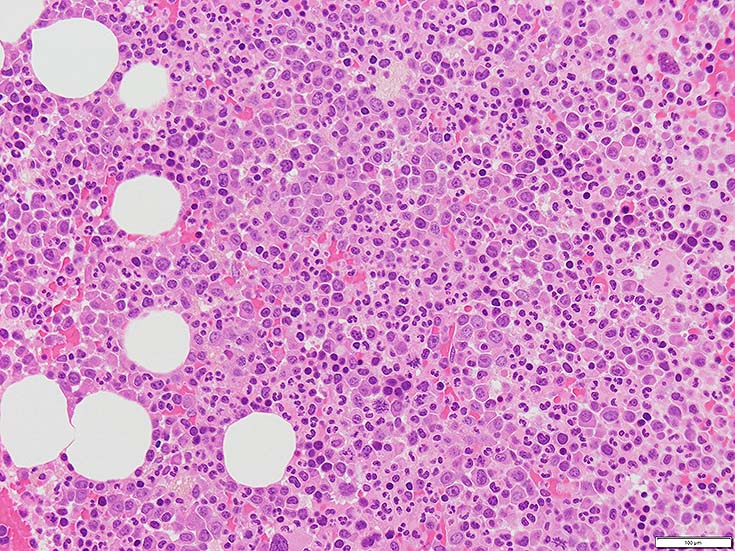

初診時の骨髄組織所見

BM-f-01HE01.jpg BM-f-01HE02.jpg BM-f-01.jpg

HE染色および, Naphtol-ASD-CAE染色した骨髄クロット組織標本-->Naphtol-ASD-CAE染色, 載せガラス法のページをみる.

70-80%のhypercellular marrow. 3系統造血細胞が認められる. Naphtol-ASD-CAE染色で赤色にそまる顆粒球系細胞増生が顕著な骨髄組織.

promyelocytesなど幼若顆粒球系細胞の集簇がみられるが, 分葉好中球他, 成熟顆粒球(Naphtol-ASD-CAE染色は薄く染まる傾向あり)も多く認められacute leukaemiaの所見ではない.

単球(Naphtol-ASD-CAE染色陰性)が密に増殖する所見は骨髄組織には認められない(*1)